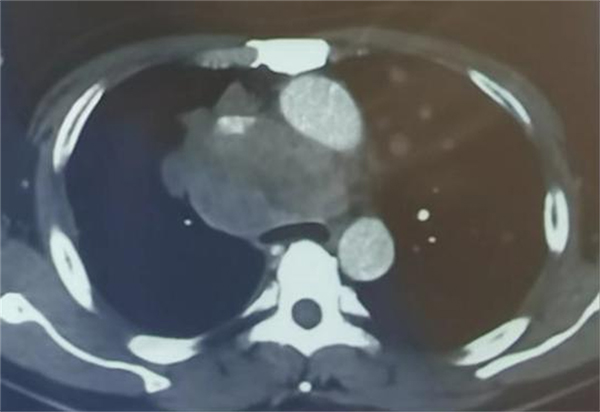

可是,疾病并不会因为疫情来临而退缩,37岁的孙先生患有肝癌,曾经做过肝部分切除术,曾经吃过靶向药物,也做过免疫治疗,但是疾病还是在进展,出现了双肺转移,年轻的孙先生已经备受病痛折磨,可病情仍在加重,出现了憋喘,越来越重,甚至不能平卧,来到应急总医院后,呼吸与危重症医学科医护人员按照防疫流程正常接诊,查胸部CT,发现孙先生的肿瘤压迫气管,气管变窄导致呼吸受阻,需立即手术解除狭窄挽救生命,但是在急诊完善检查,新冠核酸结果还没出来,如果核酸阳性,怎么办?请示周云芝主任,她坚定地说了三个字:“得救命!”这三个字对患者来说是福音!是希望!但对医护团队来说却是重大考验。于是,在院疾控处的协调下,采取最高防护级别,气管镜手术室、麻醉科、手术医生、配台护士、消杀师傅组成了一个有序配合的团队,大家通力合作打响了这台气管镜手术战。

由于占位位于前纵隔,不能平躺麻醉,否则大瘤子就会把气管压迫得更扁更窄,这样无法进行手术。所以只能坐着进行麻醉,然后躺下来,再迅速插入硬质镜,将气管管腔支撑起来,在气管内置入一枚支架,短短25分钟,气管镜室传出喜讯:手术非常成功,患者憋喘症状立刻得到缓解。当患者睁开眼睛那一刹那,家属喜极而泣。看到医护人员站在旁边,患者激动地溢于言表:“谢谢大夫,给了我第二次生命,谢谢!”